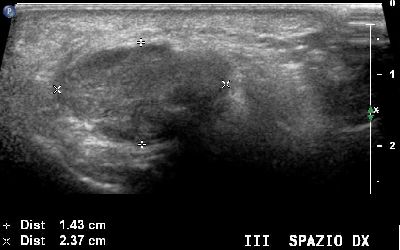

Neuroma di Morton del terzo spazio intermetatarsale (img. 01) Neuroma Morton 01

Neuroma di Morton del terzo spazio intermetatarsale (img. 02) Neuroma Morton 02

Altro neuroma di Morton del terzo spazio intermetatarsale Neuroma Morton